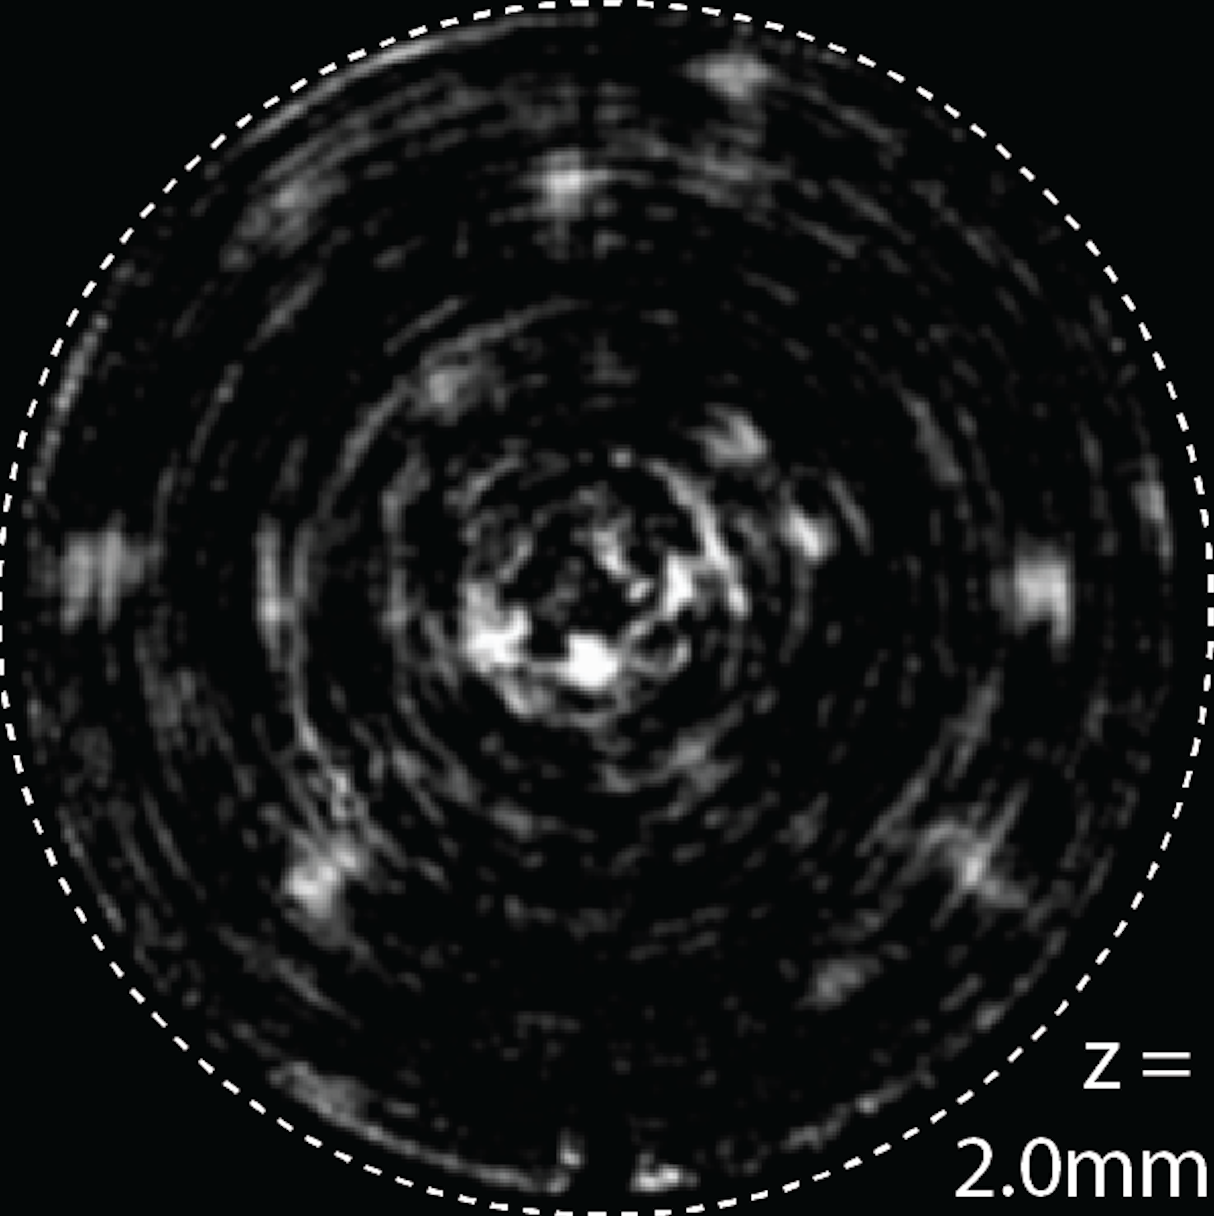

The captured images, which start as recordings of scattered light waves, are later processed by a sophisticated algorithm developed by Menon and his team into a 2-D or potentially 3-D picture.

Menon explained that the glass tube both illuminates the cells and captures reflected light from them. The picture created by that reflected light is an abstract, swirling image that doesn't look like much of anything. But the real "magic" of the research, Menon said, is a mathematical formula that distills a clear picture of the cells from that abstraction of light.

"Getting to the point of creating the image was fairly straightforward," he said. "But the real discovery was finding a way to take that jumbled collection of reflected light waves and render a very clear, high-resolution image of the cells under investigation."